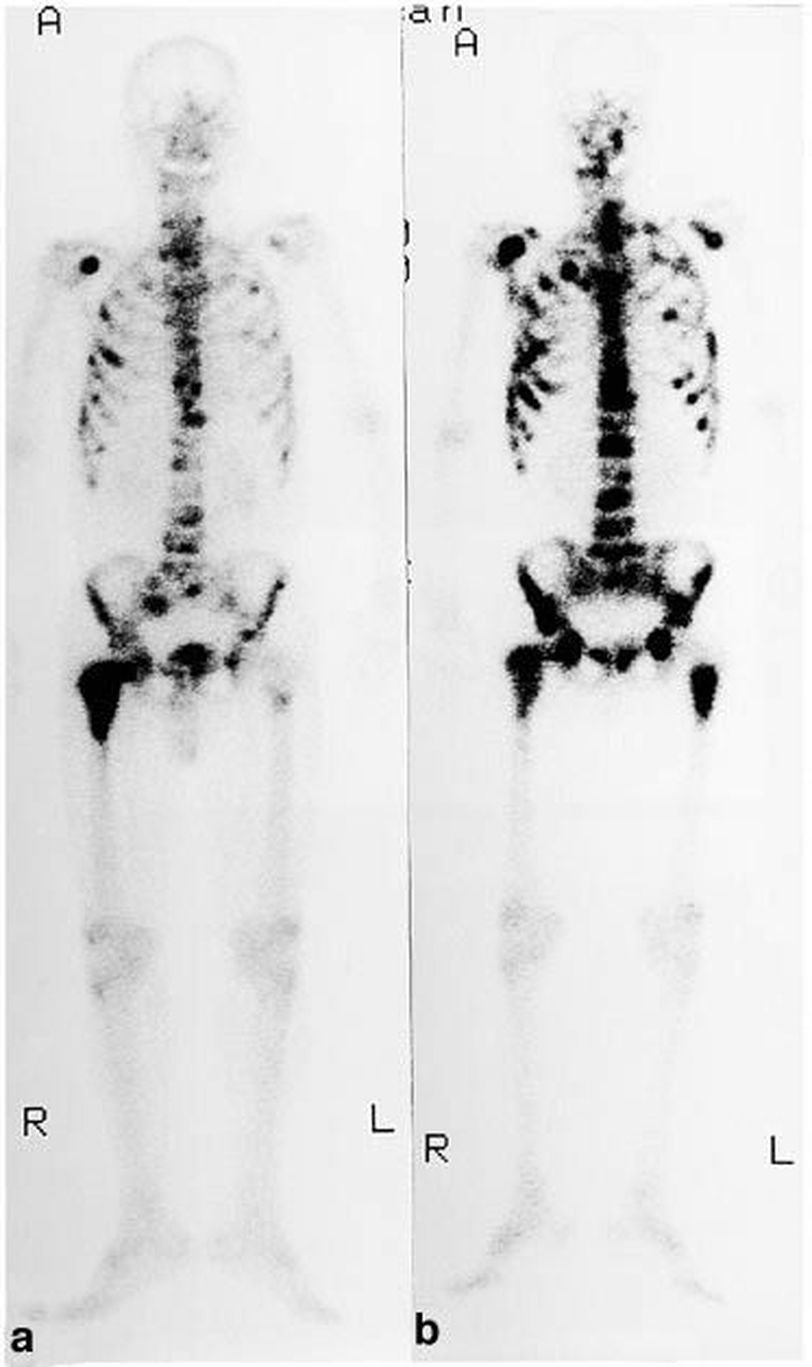

Prostate cancer, a common malignancy encountered in old aged men, frequently metastasizes to bones. As the bone scan reveals, the bones of the pelvis and spine are usually affected. The metastatic lesions are largely osteoblastic (bone forming) and hence, bone pain is the predominant feature rather than fractures. The pain can be relieved by painkillers (NSAIDS and opioids) and radiotherapy. Radiotherapy provides very good symptomatic relief for bone metastases. It also helps in relieving symptoms of spinal cord compression secondary to metastatic deposits. However, involvement of multiple areas of the bones can make radiotherapy difficult. Another technique employed for multiple bone metastases is using intravenous radioisotope of Strontium-89. This isotope preferentially deposits in bones and has been shown to be effective. However, the duration of response may not be long. Source: Bailey and Love's Short Practice of Surgery, 26th edition